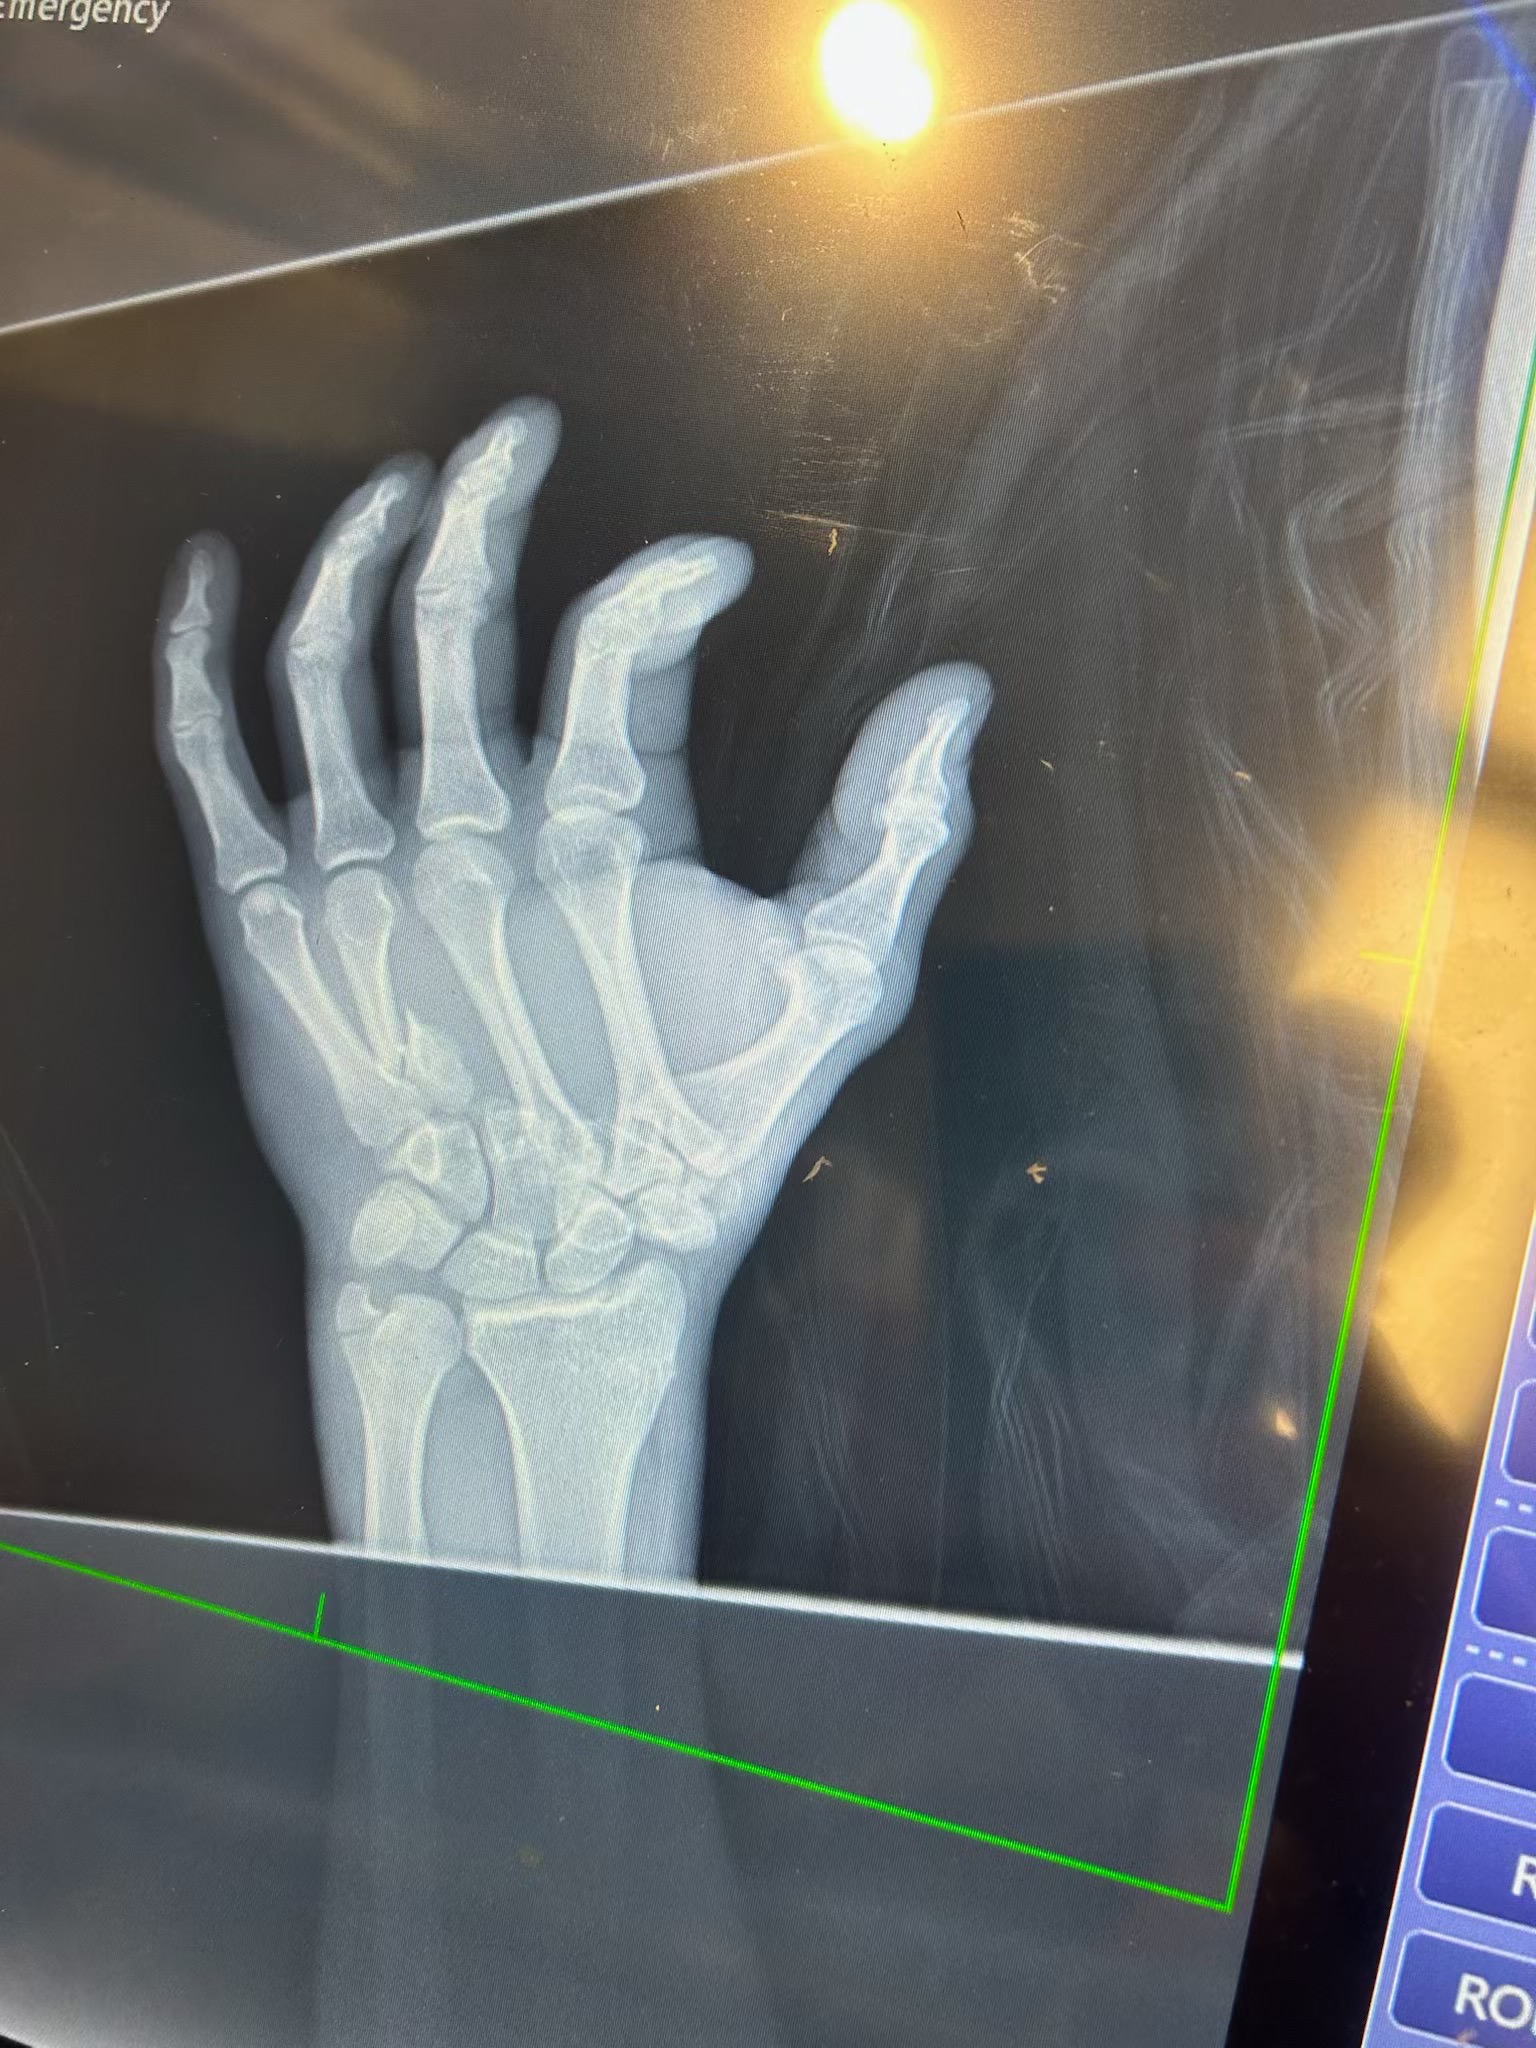

I’m helping to raise funds for Andy who was in a horrific motorcycle accident on 8/24. He has a long road of recovery ahead of him. His medical expenses are going to be huge, with ICU care, surgeries, rehabilitation, and prosthetics for his leg. He is a father of 2 young children who now has no income, and insurance will only cover so much. He’s looking at many months of care beyond just family care to help with, and no income to help cover costs. He’s dealing with the loss of his leg, surgery tomorrow on his hands and wrists, another surgery Friday for his right shoulder, and no date yet for his surgery for his right foot. Any donation would be greatly appreciated to help cover medical costs and monthly bills till he can return to work.

He had his surgery today on both hands and his right foot, went well. Lots of pins and some screws. He still has 1 more surgery scheduled for Friday on his scapulae on right side waiting for special plate to secure and fix.